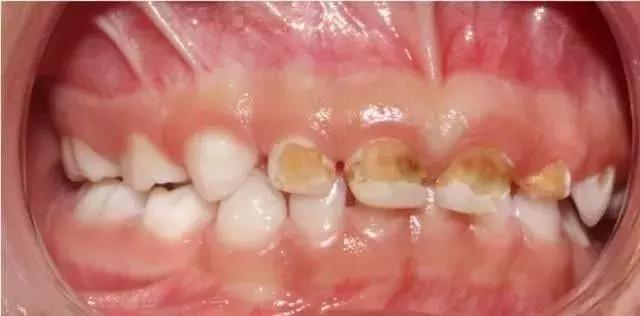

奶瓶龋最初在上颌乳切牙的唇面龈缘处出现白垩色斑点或带状脱矿,而后逐渐向下向旁边蔓延,侵蚀邻近的牙面形成环状龋,呈棕褐色,并最终发生牙冠折断,仅留下残根。

让孩子抱着奶瓶,就去上床睡觉,几周,几个月下来就会这样,妈咪不重视也不去医院治疗。。。